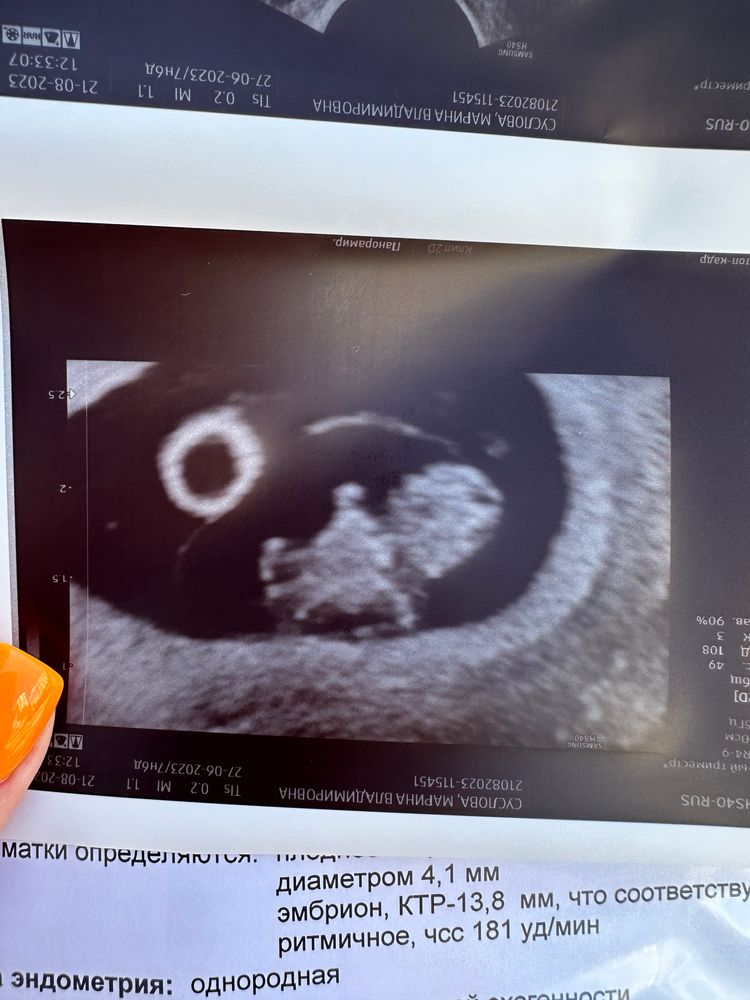

Узи в 7.6 недель

Расчет срока Б, ПДРВыкладываю узи с разницей в неделю,вроде бы все ничего,но смущает:

1)подрос желточный мешок(или погрешности изменения)у кого есть такой опыт?

2)почти не выросло плодное яйцо,хотя на прошлой неделе оно опережало свой срок.

У меня там уже целый медвежонок,как же хочется,что бы он родился☺️